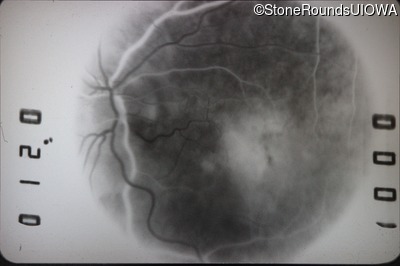

This 43 year old woman first experienced a slight loss of visual acuity at age 23. Fluorescein angiography at that time revealed some vascular leakage from the optic discs and peripheral retina. The maximum combined response of the ERG revealed a selective loss of the b-wave.

Age at visit: 43 years (Visit 2)